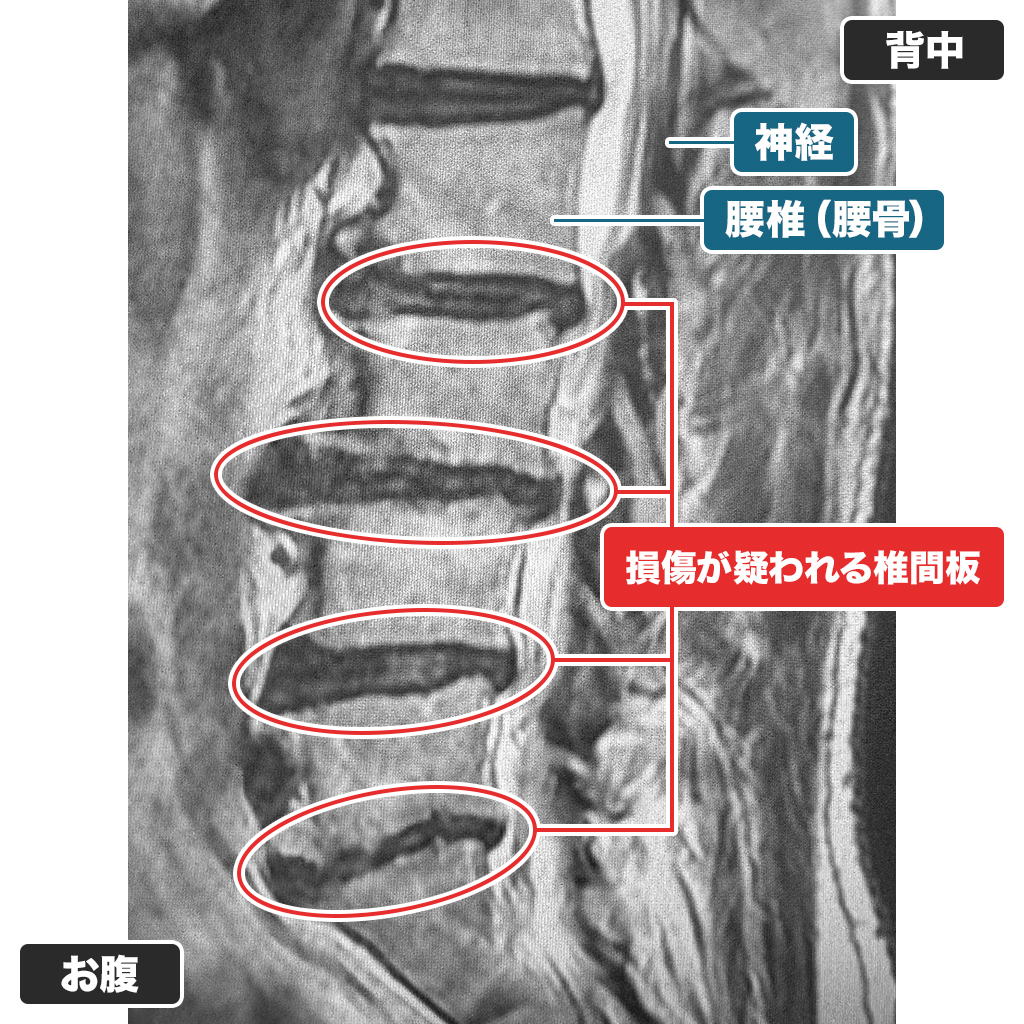

検査

腰のMRI検査ですが、複数か所で椎間板が損傷しております。椎間板容量も50%以下であることから、減圧治療(PLDDやセルゲル治療)は適応外であると判断し、ディスクシール治療をお勧めしました。